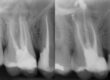

Previo al tratamiento se realiza exploración radiológica con radiografía periapical y CBCT para tener una visión tridimensional del caso. (Fig. 1) En las imágenes se ve que las raíces tienen imágenes radiolúcidas por lo que se sospecha de la existencia de conductos omitidos. Se descarta la existencia de fisuras radiculares. (Fig. 2)

Fig. 2: Plano axial del tercio medio donde se puede observar la existencia de cortical alrededor de las raíces,

descartando la presencia de fisuras o fracturas verticales.